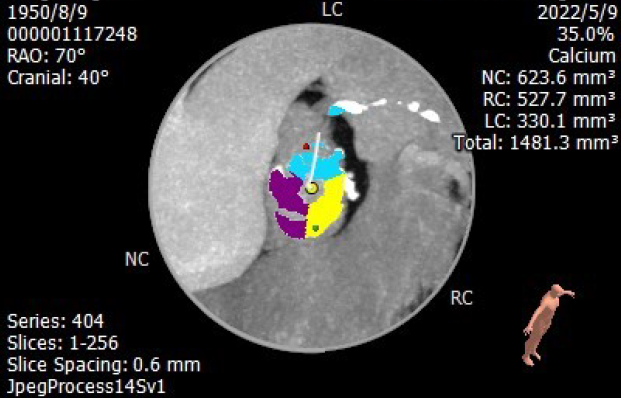

极重度钙化,瓣叶钙化增厚且长

钙化积分1481mm3

钙化从瓣环延伸至流出道10.8mm

此次手术患者病况非常复杂:刚入院时患者左心室功能衰竭(EF值25%), 同时患有慢性肾功能不全。主动脉瓣极重度钙化(钙化积分1481mm3)同时伴有二尖瓣、主动脉瓣反流。解剖结构方面,患者左冠高度低、瓣叶长存在冠脉阻塞风险,同时在大弯侧有瓣叶团块钙化,提升了跨瓣的难度。